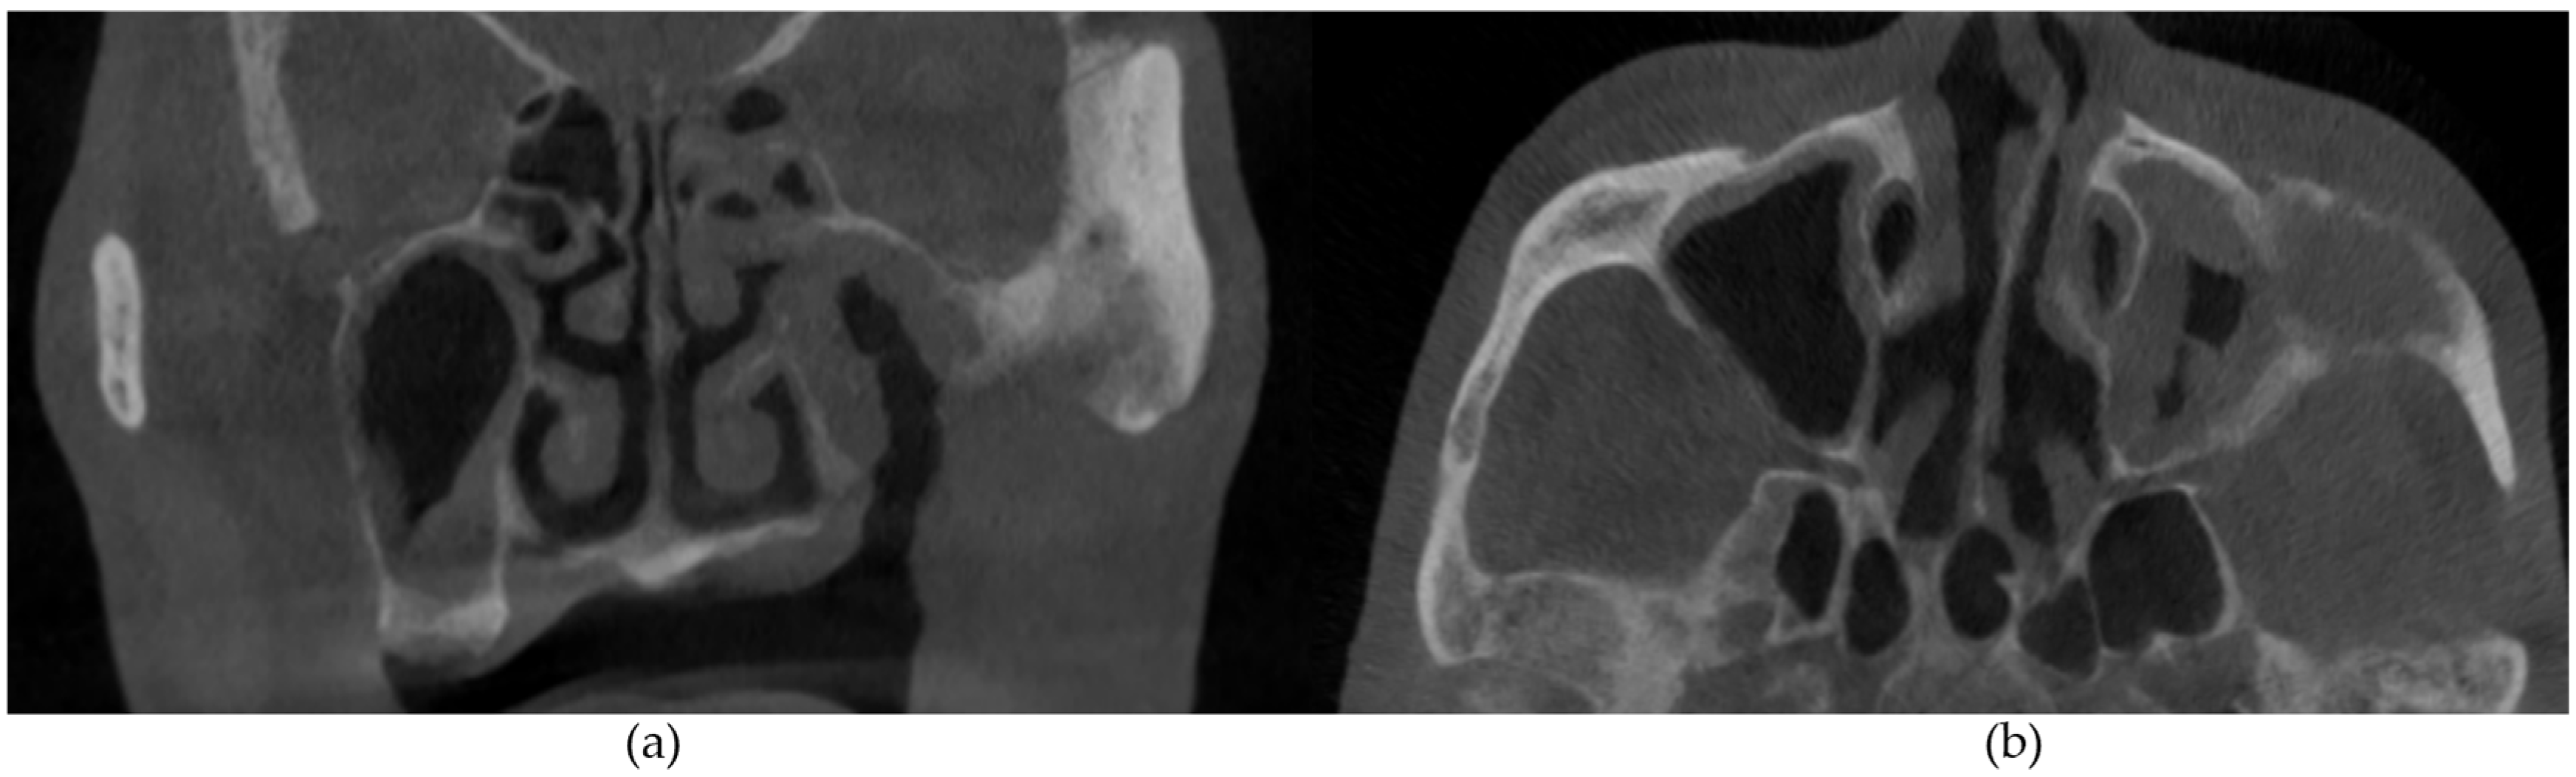

Figure 2. (a) Sagittal and (b) axial sections demonstrating generalized osteosclerosis of the mandible. Arrow demonstrates mild mental foramen narrowing.